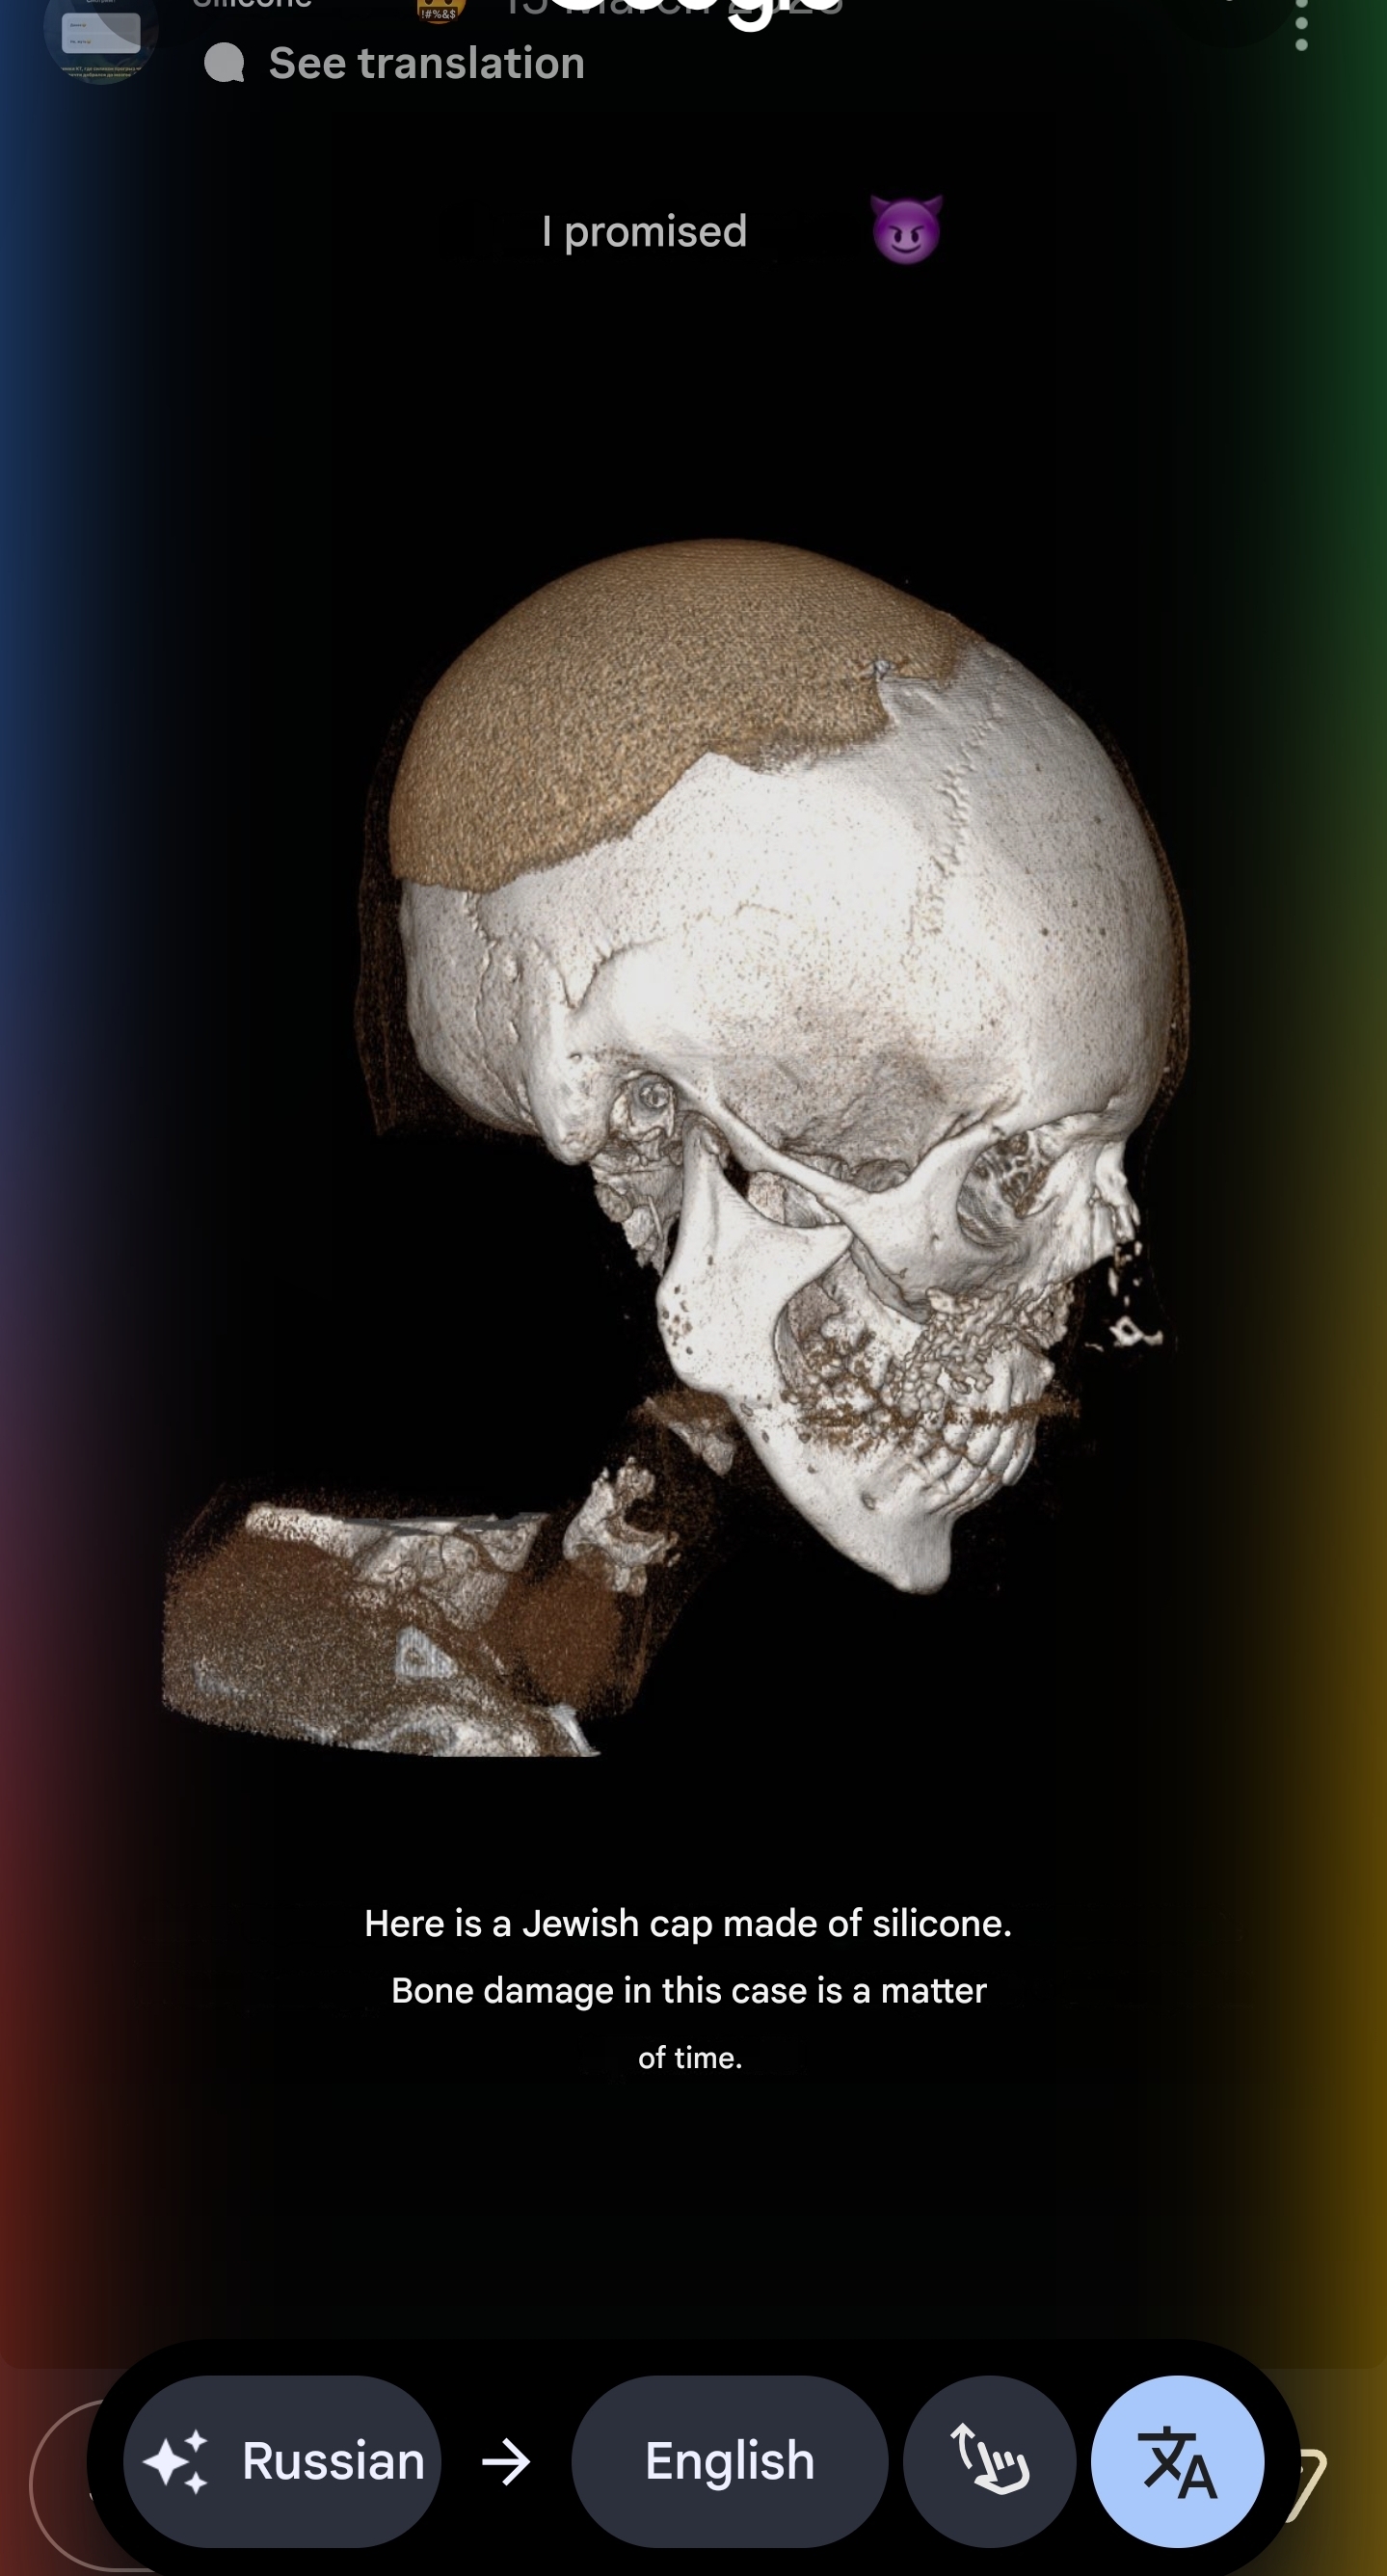

if you could recommend me surgeon in Russia, I'd be very grateful. I found 2 good ones andreishchev who is responsive and Kurakin who ignored me on instagram but i joined their telegram channel